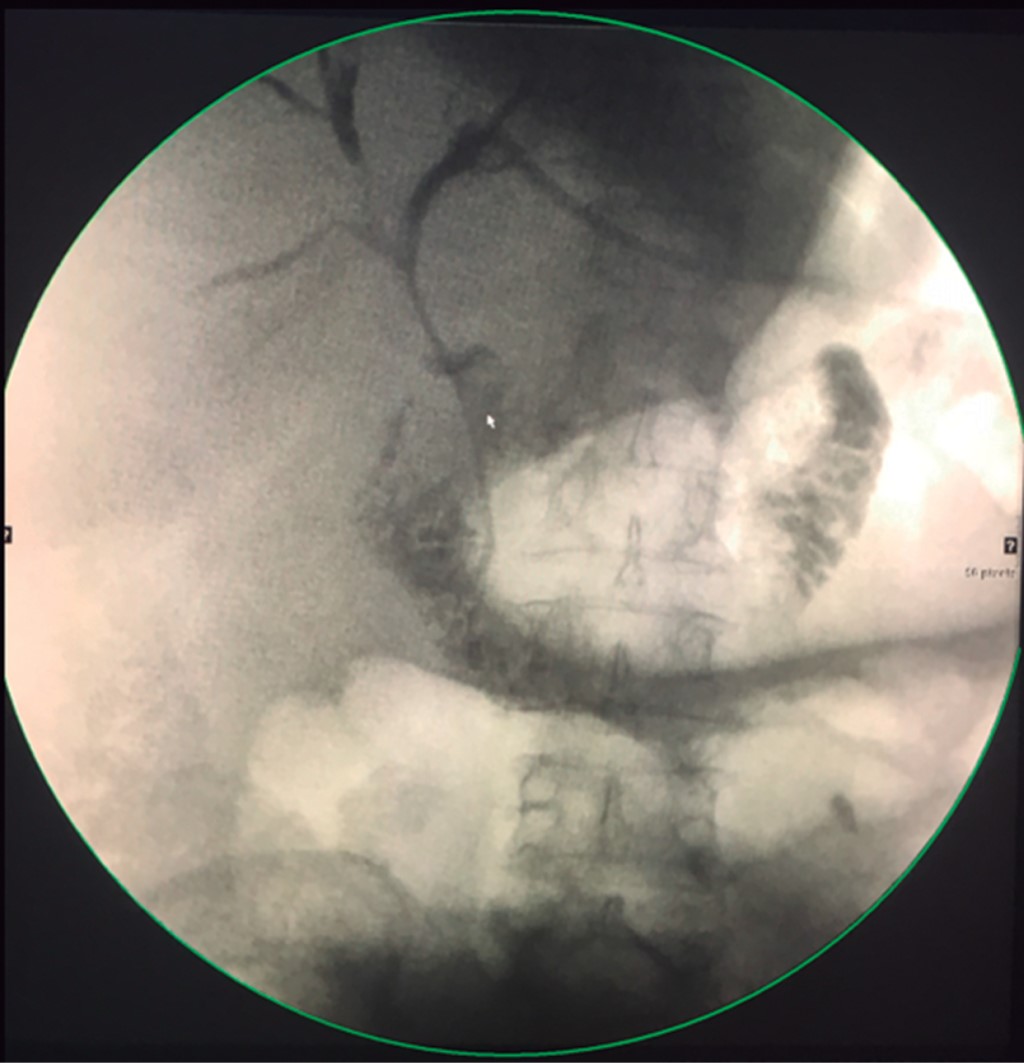

The DBPATP protocol consists of the installation of a mixed biliary catheter, i.e., one that manages to frank the stricture and place fenestrae in both the biliary and intestinal lumen (Figure 1), usually with an initial diameter of 8.5 or 10 Fr that is replaced every two months by a larger French (Fr) (2 Fr of advance per session) until reaching a variable diameter depending on the stenosed duct, 14 Fr if it is only a right or left duct and between 18 and 22 Fr if it is the confluence. The catheter is kept closed because its mixed position allows biliary flow into the intestine through the fenestrations and is only opened when cholangitis is suspected.

Figure 1